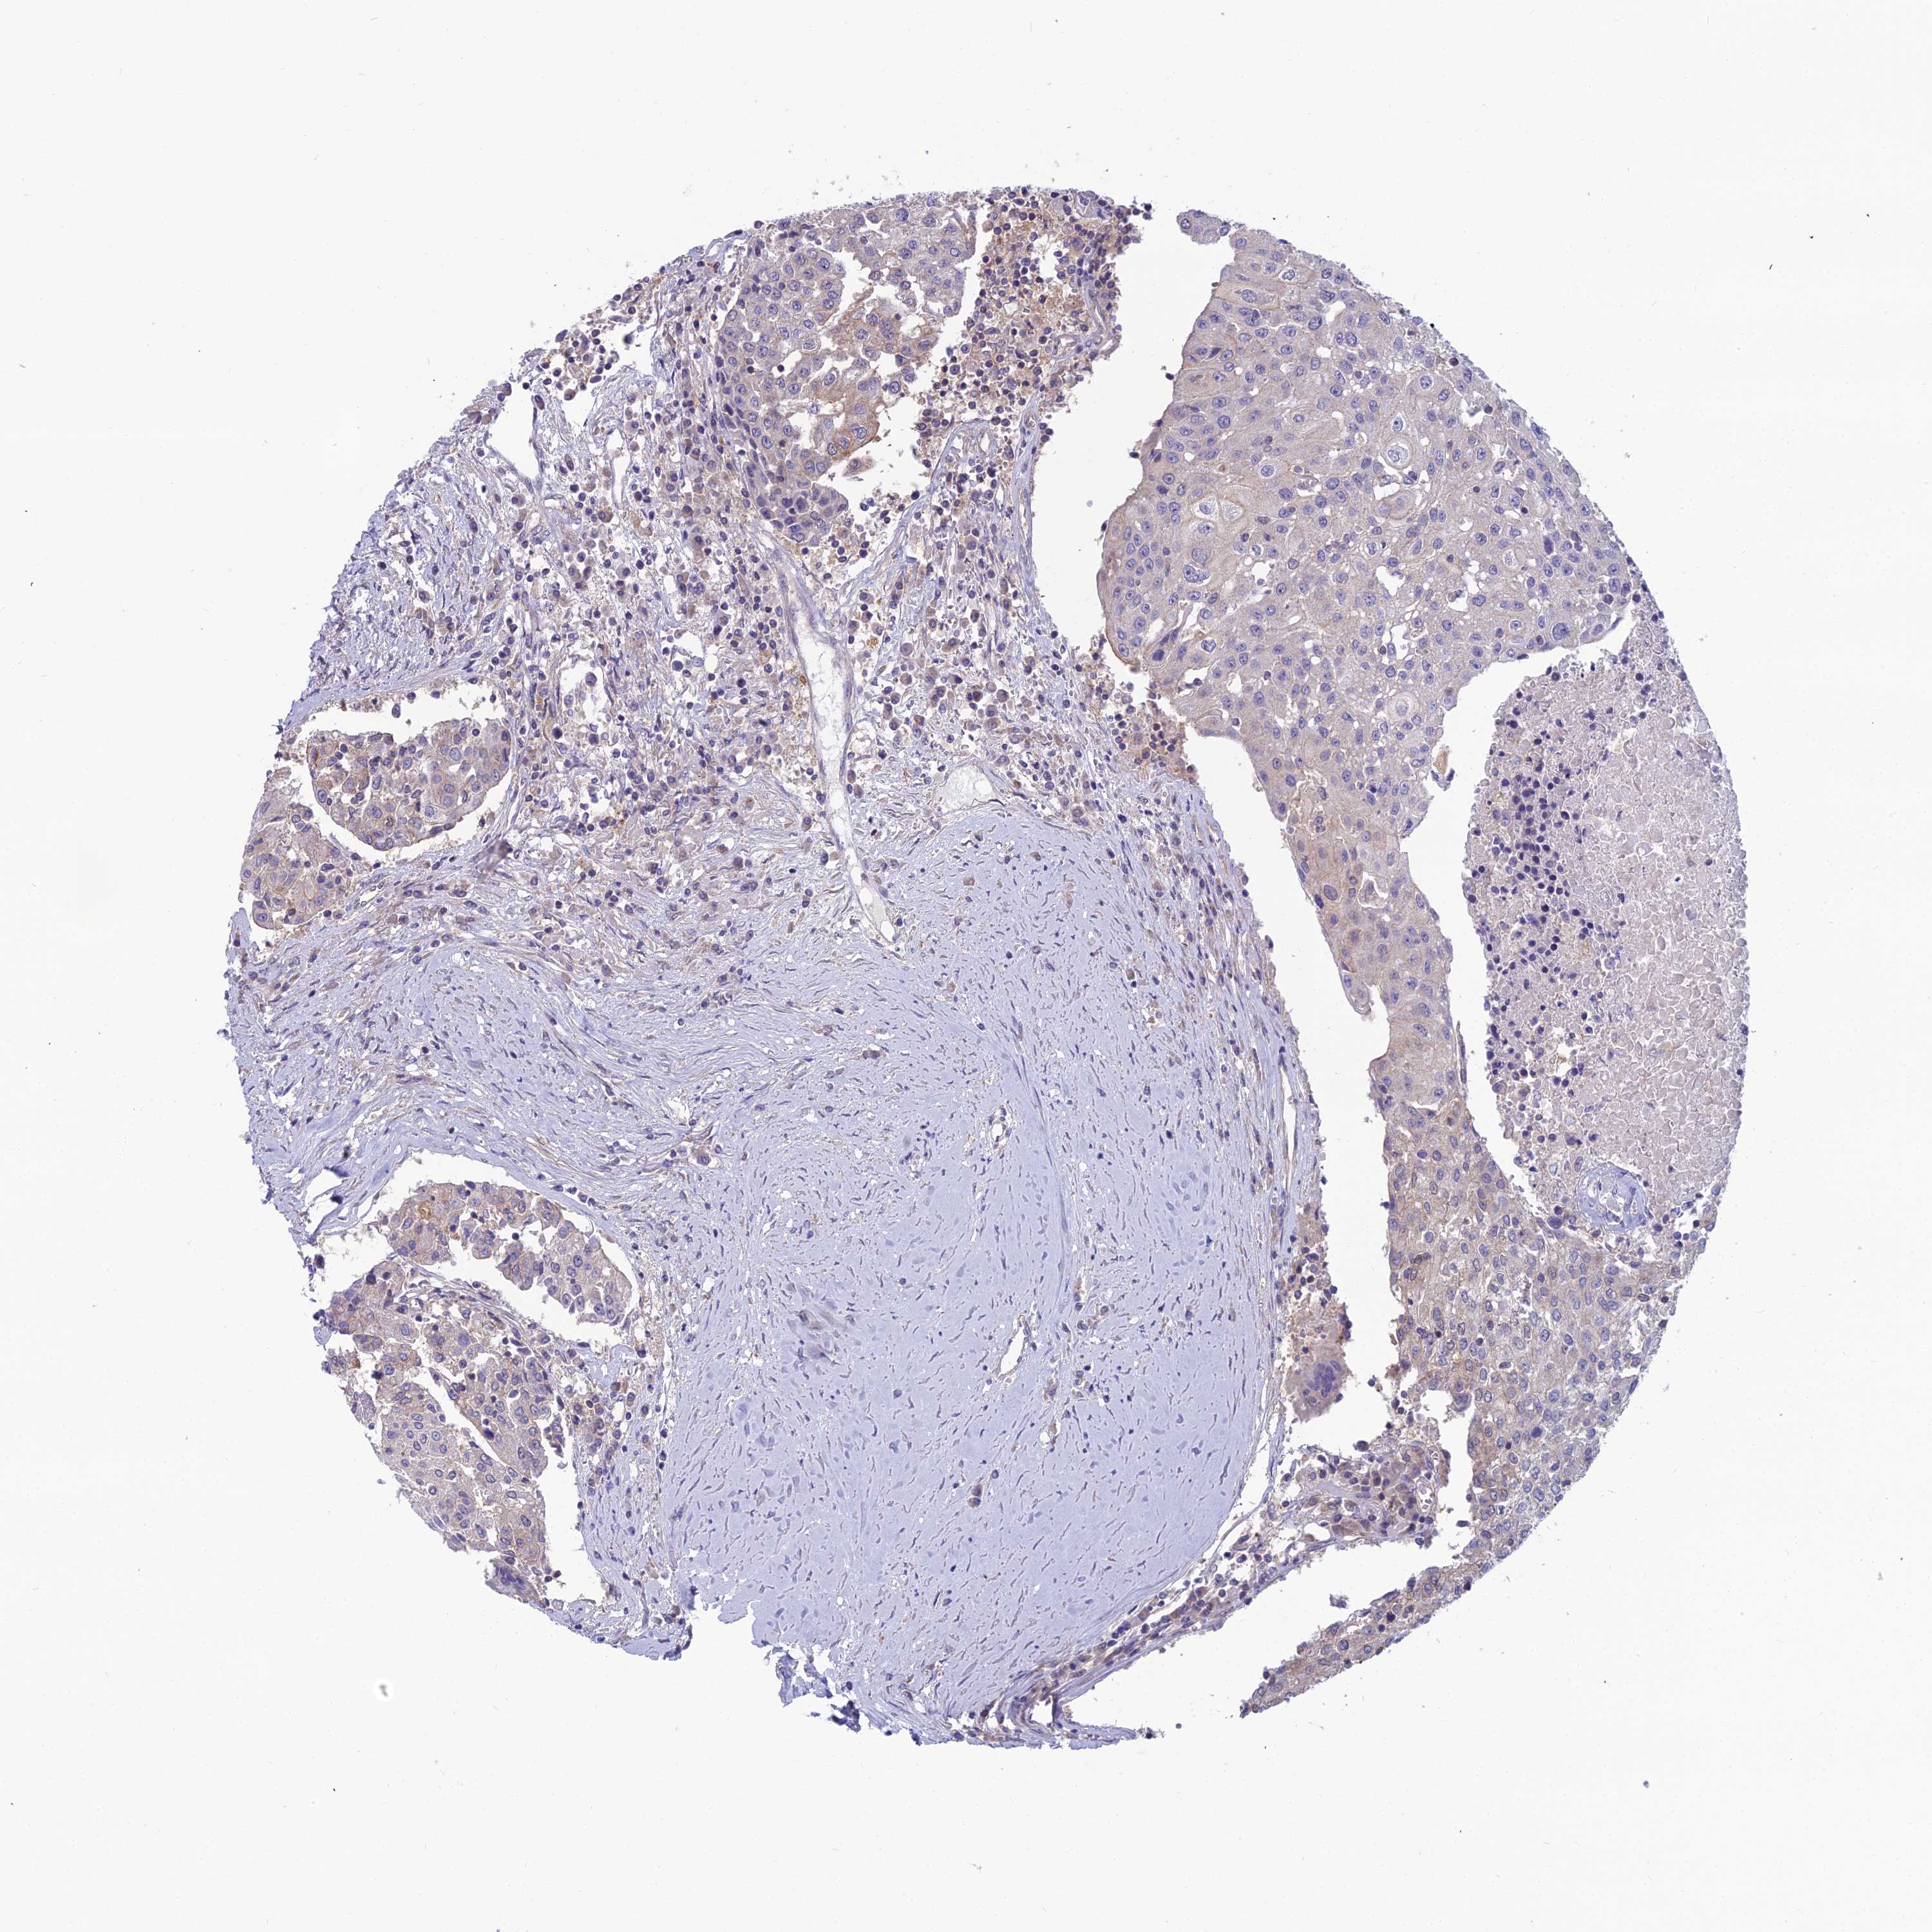

UROTHELIAL CANCER - Protein expressioni

A mouse-over function shows sample information and annotation data. Click on an image to view it in a full screen mode. Samples can be filtered based on level of antibody staining by selecting one or several of the following categories: high, medium, low and not detected. The assay and annotation is described here.

Note that samples used for immunohistochemistry by the Human Protein Atlas do not correspond to samples in the TCGA dataset.

Antibody stainingi

Antibody staining in the annotated cell types in the current human tissue is reported as not detected, low, medium, or high, based on conventional immunohistochemistry profiling in selected tissues. This score is based on the combination of the staining intensity and fraction of stained cells.

Each image is clickable and will lead to virtual microscopy that enables deeper exploration of all samples and also displays staining intensity scores, fraction scores and subcellular localization as well as patient and tissue information for each sample.

Antibody HPA041404

Antibody HPA048250

Urothelial carcinoma, High grade

Urothelial carcinoma, Low grade